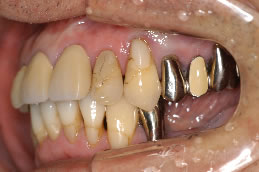

患者さんは66歳(男性)左下臼歯部欠損で咀嚼機能回復の為来院。

写真1〜4はそれぞれ術前・後の左側口腔内写真とレントゲン画像です。

写真1(施術前)

写真3(施術後)